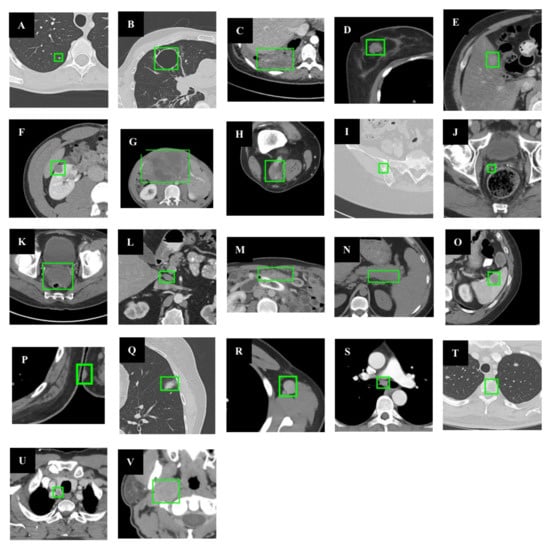

This paper employs a dataset that includes eight types of CT images: abdomen (lesions in the abdominal cavity that are not in the kidney or liver), soft tissue (various lesions in the body wall, such as fat, head, muscle, limbs, neck, and skin), liver, lung, mediastinum, bone, pelvis, and kidney. In Figure 1, it is demonstrated that the dataset has the following characteristics.

Figure 1.

Dataset visualization (the green box marks the location of the lesion). The following sample lesions are displayed to demonstrate the tremendous diversity of the dataset: (A) is a lung nodule; (B) is a lung cyst; (C) is costophrenic sulcus (lung) mass/fluid; (D) is a breast mass; (E) is a liver lesion; (F) is a renal mass; (G) is a huge abdominal mass; (H) is a posterior thigh mass; (I) is an iliac sclerotic lesion; (J) is a perirectal lymph node (LN); (K) is a pelvic mass; (L) is a periportal LN; (M) is an omental mass; (N) is a peripancreatic lesion; (O) is a splenic lesion; (P) is a subcutaneous/skin nodule; (Q) is opacity of ground glass; (R) is an axillary LN; (S) is a subcarinal LN; (T) is vertebral body metastases; (U) is a thyroid nodule; (V) is a neck mass.

Due to the above characteristics of this dataset, various data augmentation methods are adopted in this paper to enhance the model’s detection performance.